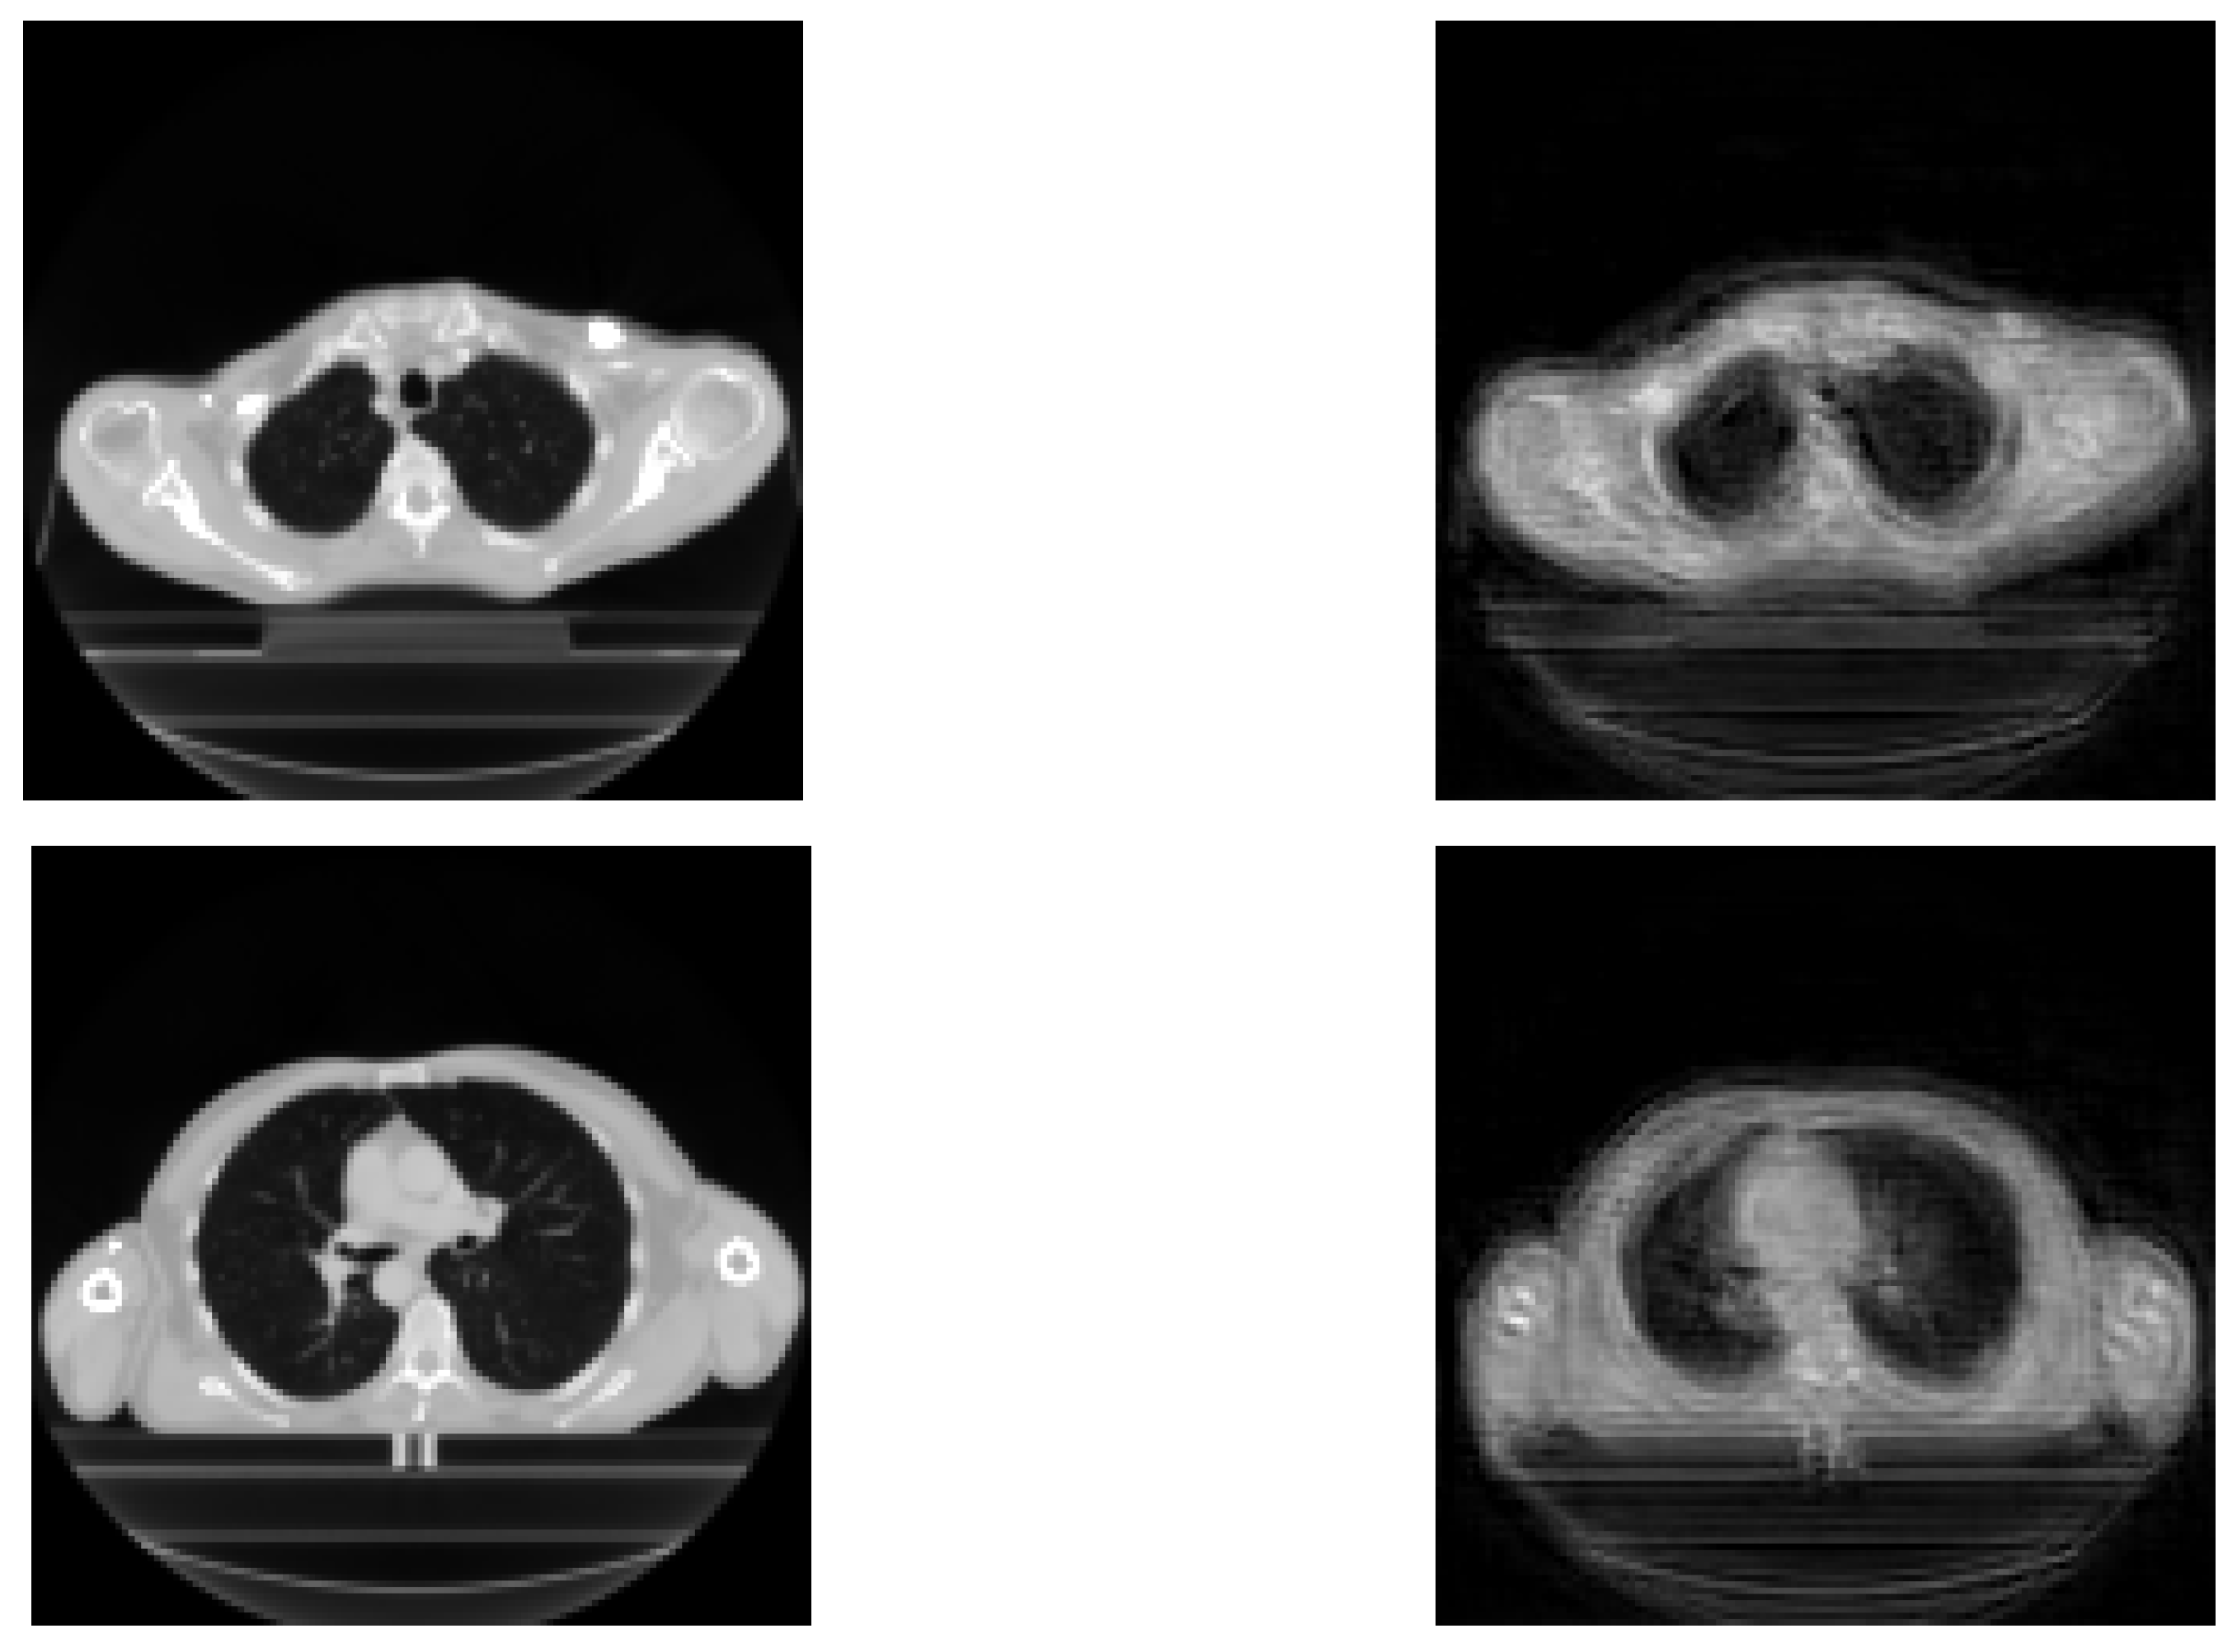

Deep learning has been widely developed in the medical field for classification or segmentation tasks [25,26,27]. Classification can be used to identify automatically the kind of cancer from which the patient is suffering [28,29] or the relevant outcomes after treatment, such as survival expectation [30] or relation to the treatment [31]. Recurrence in cancer after treatment is one of the main concerns for physicians [32], as it can dramatically impact the outcome for patients and their life expectancy. It would be beneficial for treatment selection if one could predict whether a recurrence will occur. Some studies have been carried out using CT scan images and clinical data. To our knowledge, there is no article using Tsallis–Havrda–Charvat for recurrence prediction [17]. The novelty of this article lies in the performance comparison of Shannon and Tsallis–Havrda–Charvat entropies in the context of cancer recurrence prediction with CT scan data combined with clinical information for patients affected by head and neck (H&N) or lung cancers (examples of the analyzed CT images are displayed in Figure 1). Moreover, we decided to study the parameter value in particular to examine its impact in order to predict these recurrences in both kinds of cancer. As medical data are generally scarce, the choice of a good entropy is important even if it can improve the performance only by 1 or 2 percent.

Figure 1. Input images: head–neck CT (above) and lung CT (below).